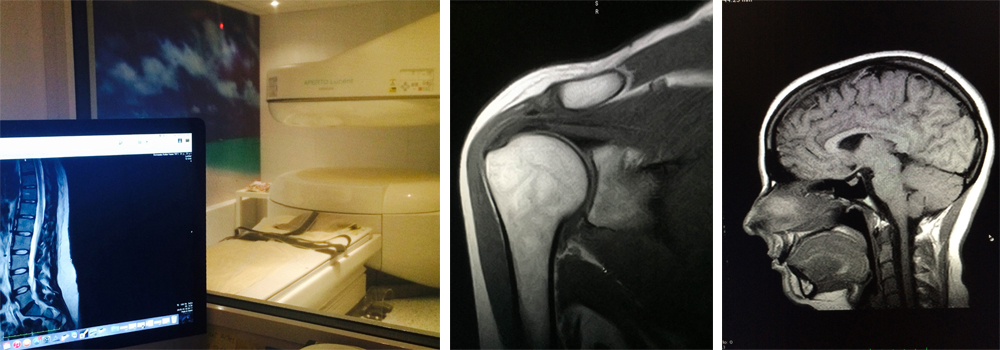

UNIDAD DE DIAGNÓSTICO POR IMAGEN Y RADIODIAGNÓSTICO

RESONANCIA MAGNÉTICA ABIERTA DE ALTA RESOLUCIÓN

Resonancia Magnética abierta de Alta resolución: 2048 x 2048 pixeles - 256 cortes – 1mm de espesor potencial

Disponemos de una amplia capacidad de estudio al servicio de pacientes y profesionales médicos que lo requieran. Llevamos el diagnóstico a un nivel superior utilizando una tecnología más amable para el usuario, al disponer de una configuración abierta de alto rendimiento para estudios más detallados, más exactos, más minuciosos y de las máximas garantías, para llegar al detalle que se precisa sin escatimar esfuerzos y a cualquier parte del cuerpo que sea necesaria.

Gracias a esta avanzada tecnología de campo magnético permanente, les proporcionamos estudios diagnósticos a 2048 x 2048 píxeles de resolución de imagen, con un alcance potencial de 256 cortes a 1 mm de espesor mínimo. La función de separación de grasa y agua se realiza directamente durante el estudio, al igual que en las resonancias más avanzadas, y el sistema RADAR que posee, corrige los movimientos involuntarios del paciente evitando así errores durante la realización de la prueba. Analizamos el eco de retorno con un avanzado software permitiendo imágenes más nítidas, más estables y de mayor contraste, como la tecnología de predicción y supresión de las corrientes de remolino (ECC system) incorporadas en el propio imán. Con todo ello el potencial de diagnóstico aumenta exponencialmente, permitiéndonos localizar y analizar los artefactos más pequeños que determinada patología pueda originar. Leer más...